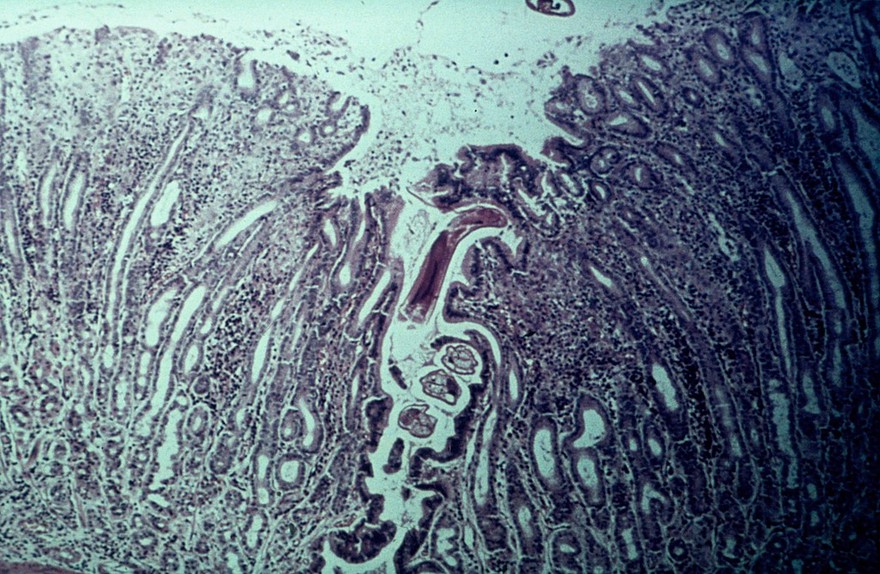

O.ostertagi in the gastric gland (cow)

Bovine abomasum: nodule due to o.ostertagi

Bovine abomasum: acute ostertagiasis. (Note: